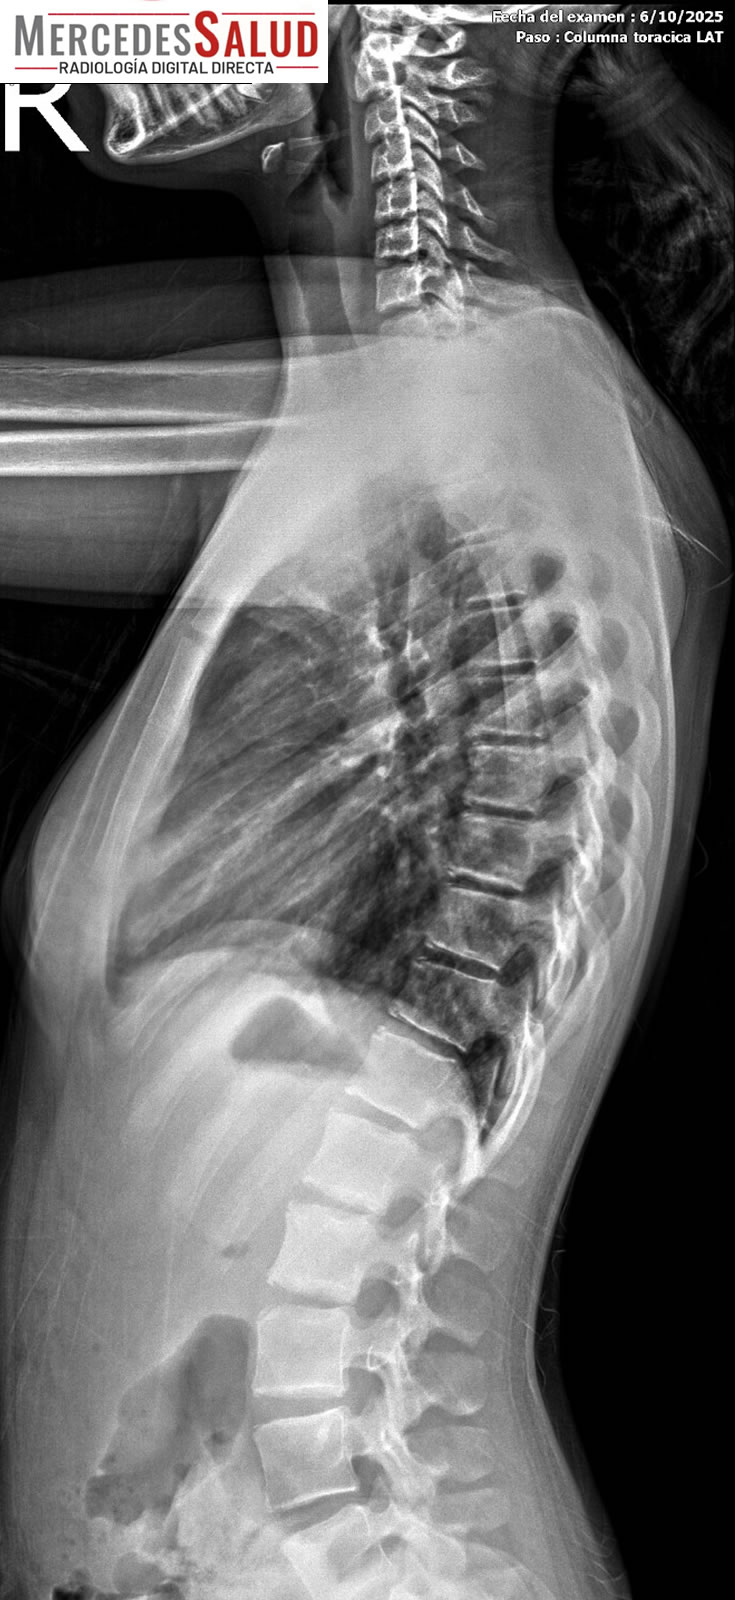

Además del tomógrafo dental, que realiza panorámicas dentales y tomografías, y permite realizar laminografías de la articulación temporomandibular (ATM) y placas de macizo facial para casos como fracturas, el servicio también ofrece estudios especializados como espinogramas y mediciones de miembro inferior con el equipo Pimax. Estos estudios de alta calidad son muy requeridos por traumatólogos de la ciudad y zonas aledañas. La calidad de imagen es tal que, según el Lic. Quiroga, pacientes de ciudades vecinas viajan a Mercedes para ser atendidos.